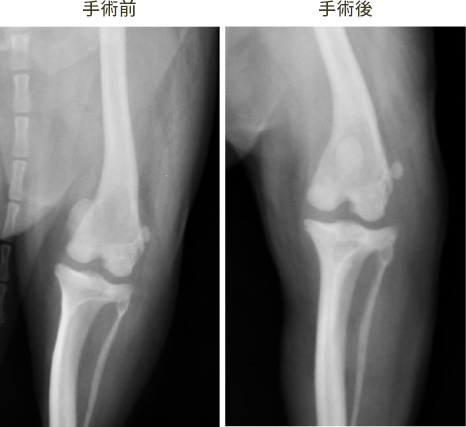

人では、外傷で発生することが多いですが、動物では日常生活で突然足を上げる疾患です。

当院では従来の手術方法である、ラテラルスーチャーだけではなくより高度なTPLOも実践してい ます。